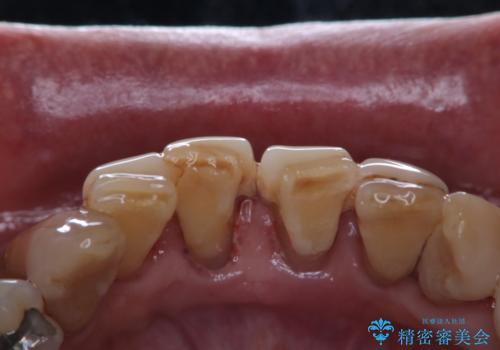

- 忙しくて、しばらくクリーニングをしていないため、全体的にしっかりとクリーニングしてほしいとのことでした。PMTC60分コースを行いました。

プラークが放置されると、そこで病原菌が繁殖し始めます。そうなるとバイオフィルム(歯面に強固に付着したばい菌の膜)になり、歯肉に炎症が生じ歯周病の引き金となります。

プラークやバイオフィルムといった細菌などを放置すると歯石となります。歯石になってしまうと歯磨きでは取り除くことができないため、歯科医院にて専門的な機械や材料を使用してクリーニングを受ける必要があります。